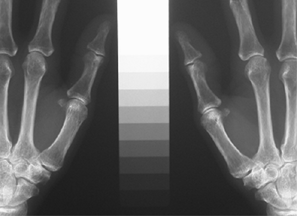

両手のX線写真手からデジタル画像処理を行い 高価な測定法(図2)は行えません。

骨密度(図1)を測定します。

図1 図2